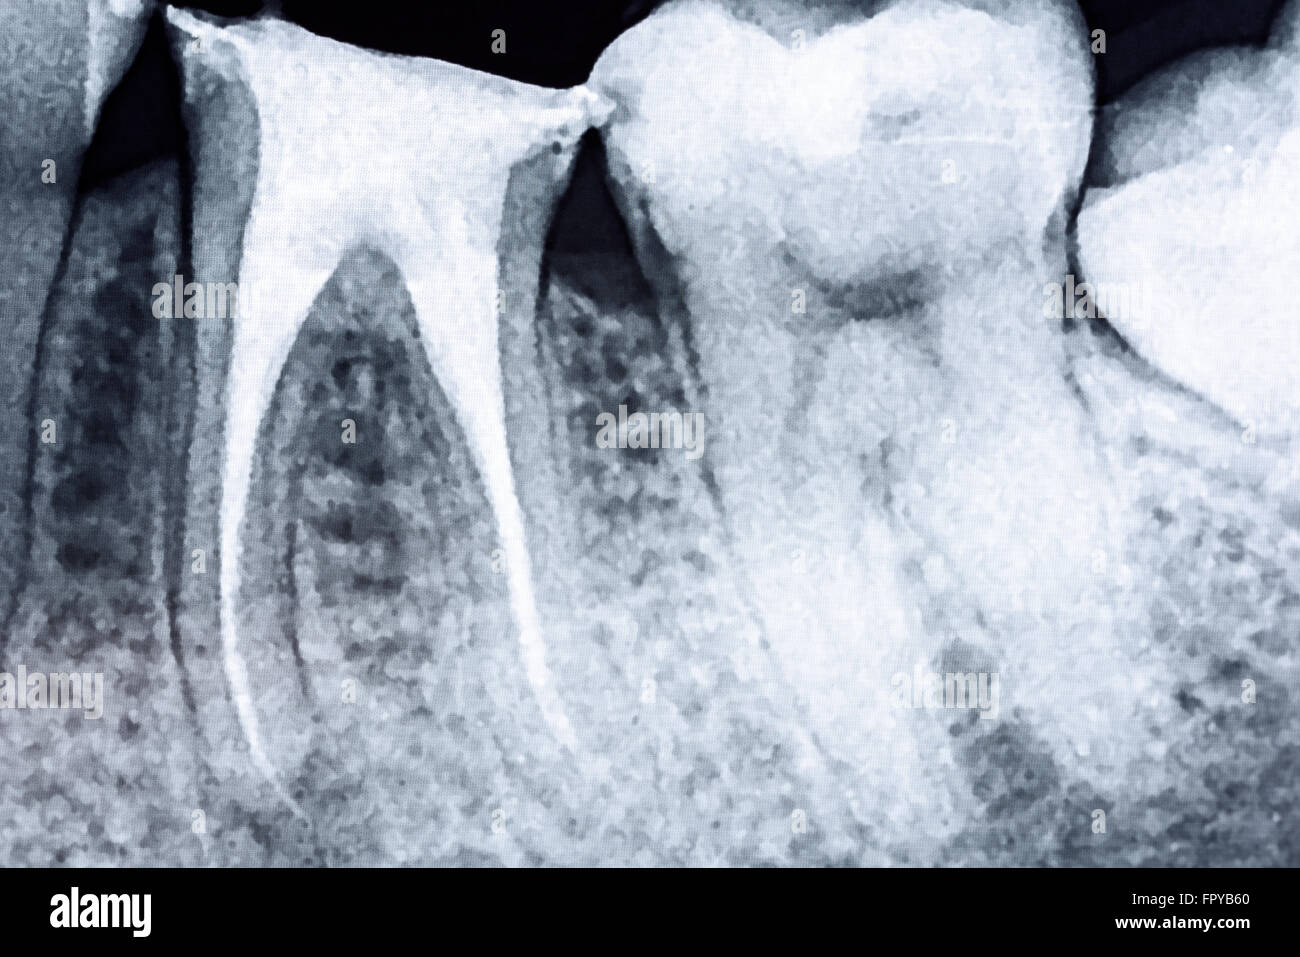

Good Root Canal X Ray .   a root canal (endodontic therapy) is a dental treatment for infections in tooth pulp, the innermost layer of your teeth.   features that are visible on a radiograph which influence success include the number and curvature of canals and.   they are used for diagnosis, preoperative assessment and patient communication, interpretation of root and root canal system.   the reason for needing a root canal is often a recurrent decay that is too close to the nerve and/or the infection at the root of the tooth, called apex, the.   a patient undergoing endodontic treatment should expect to have radiographs taken at several stages during treatment.  the aim of this systematic review was to identify the guidelines on endodontics which make recommendations.